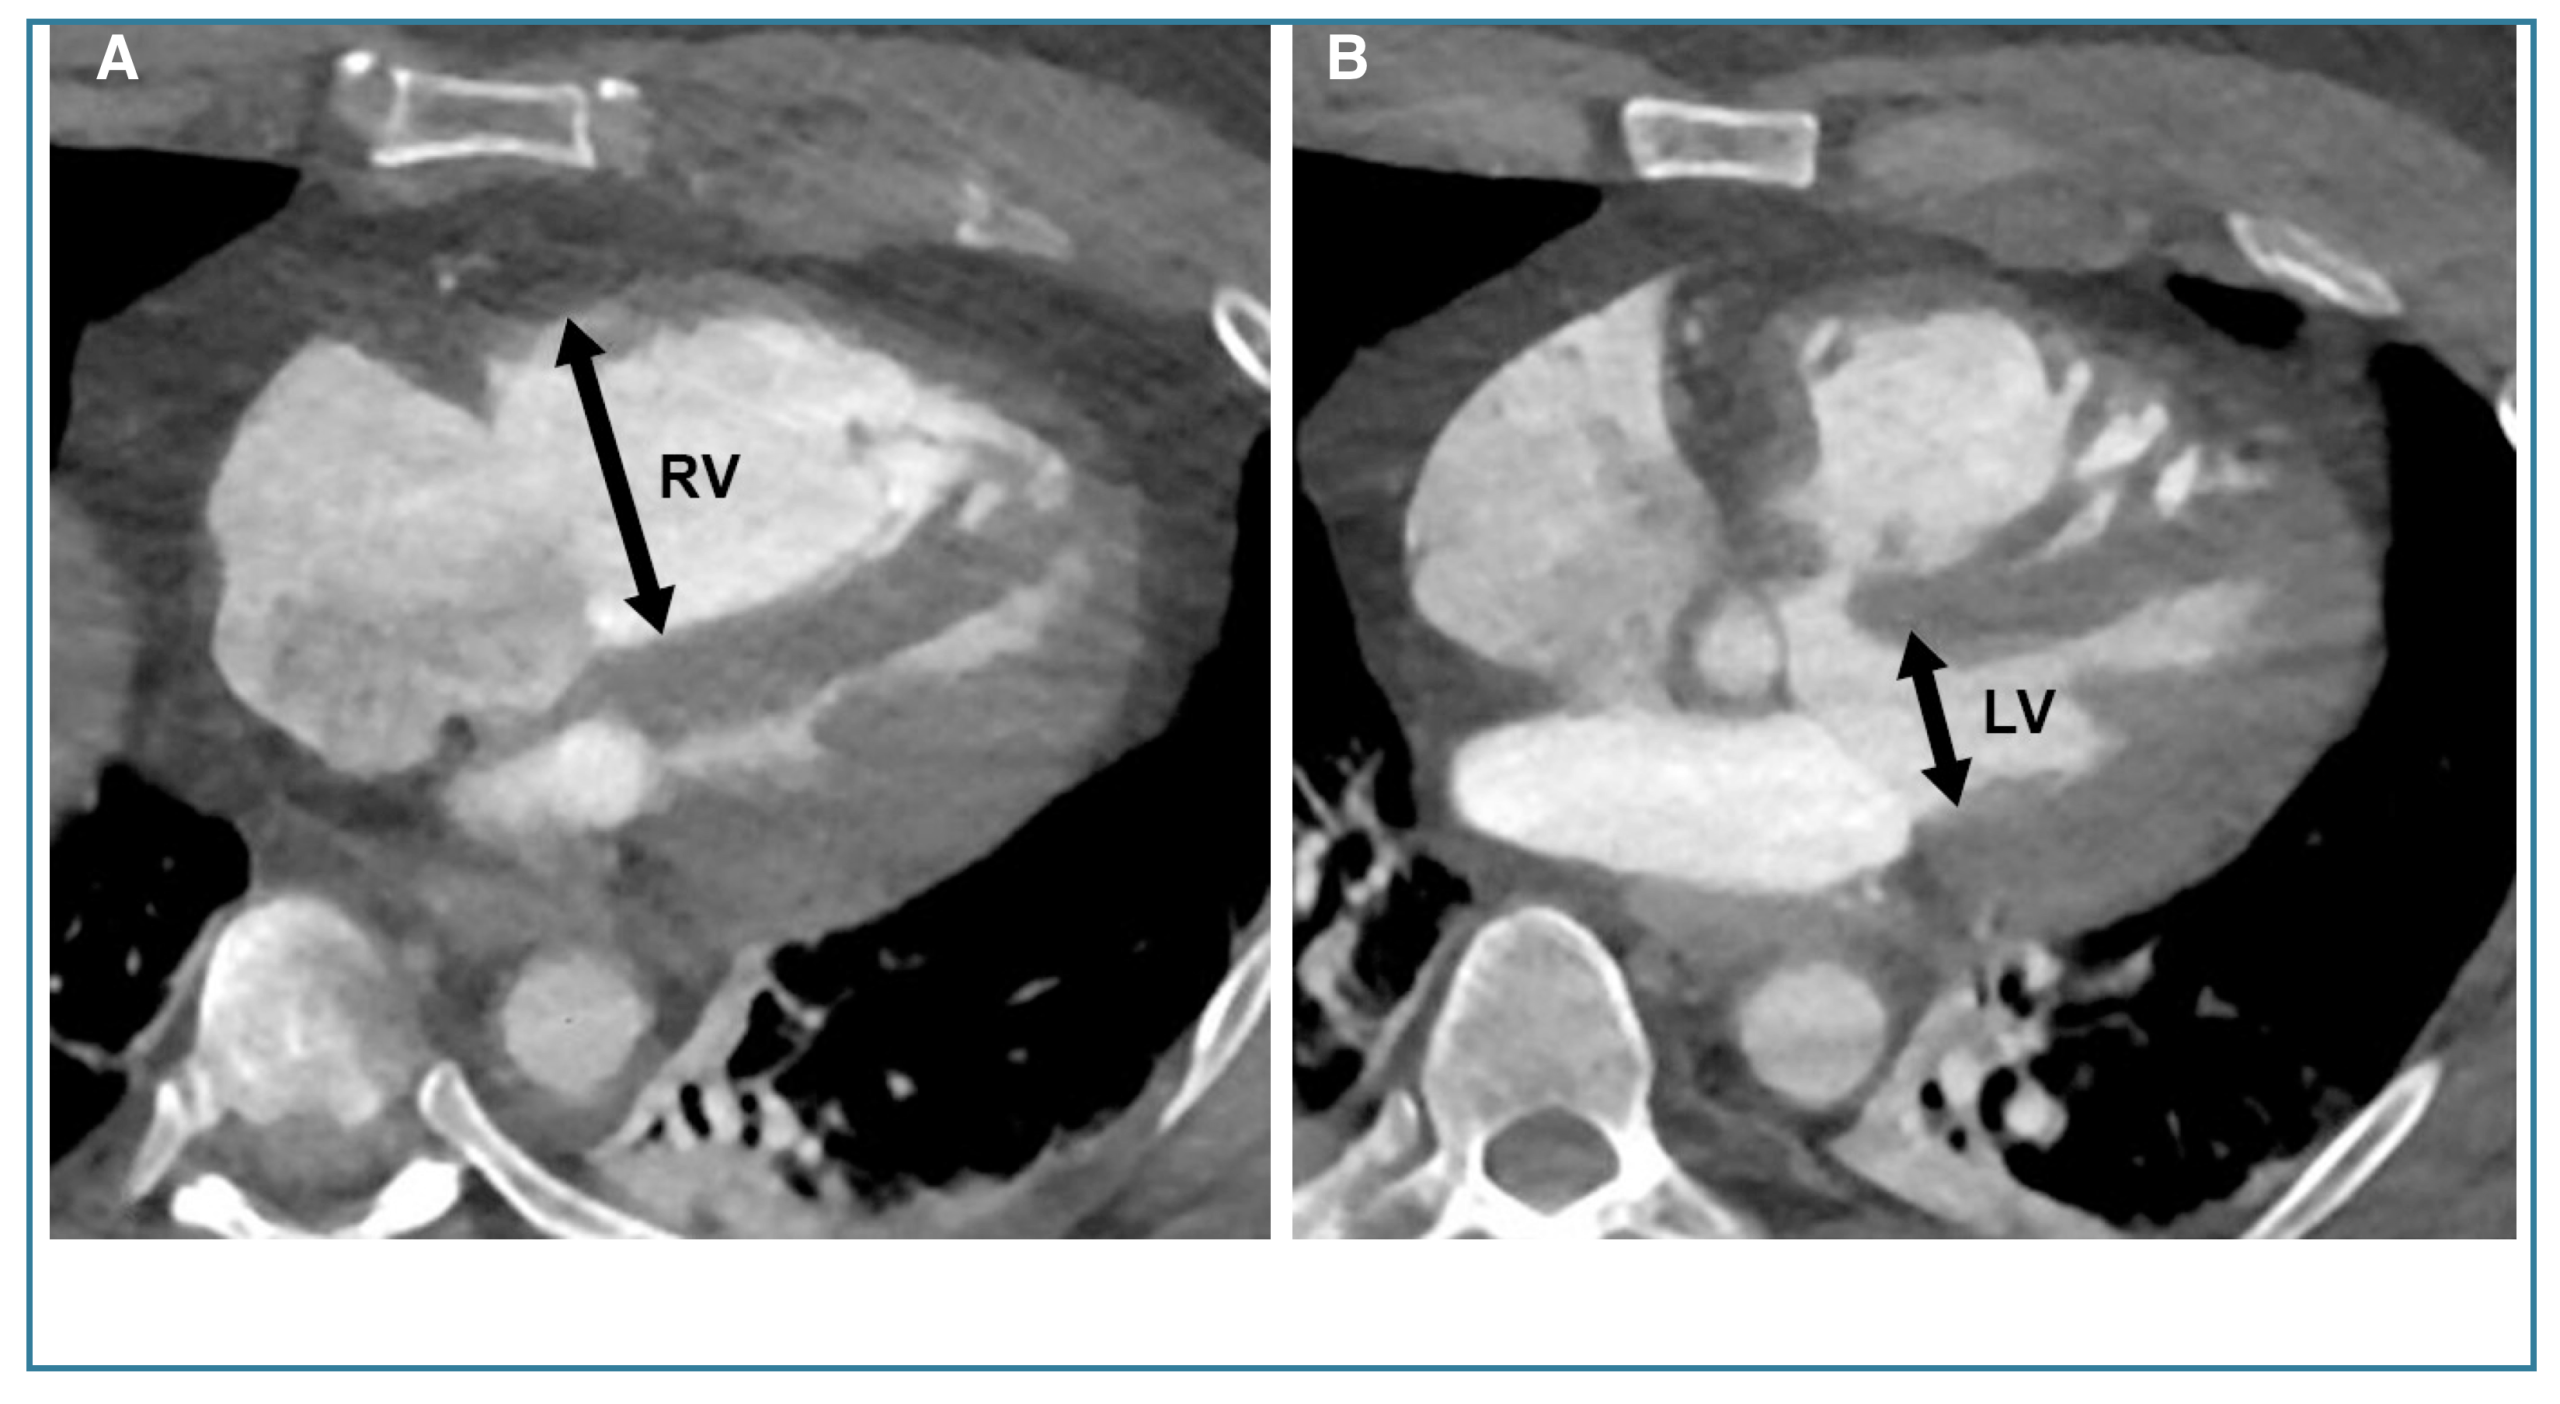

◾️Right Ventricular (RV) Enlargement & Strain

- Acute RV strain/dilatation can and does occur with a large, hemodynamically significant acute PE. It’s a sign of severity.

- Key CT Signs of Acute RV Strain:

- RV/LV Diameter Ratio > 1.0 (measured in the axial plane at the widest point). This is the most commonly used measure.

- Septal flattening or bowing into the left ventricle (LV), giving the LV a “D-shaped” appearance.

- Reflux of contrast into the inferior vena cava (IVC) and hepatic veins.

- Crucial Point: In acute PE, this RV enlargement is often disproportionate to the visible clot burden, reflecting acute pressure overload. It can be reversible with treatment.